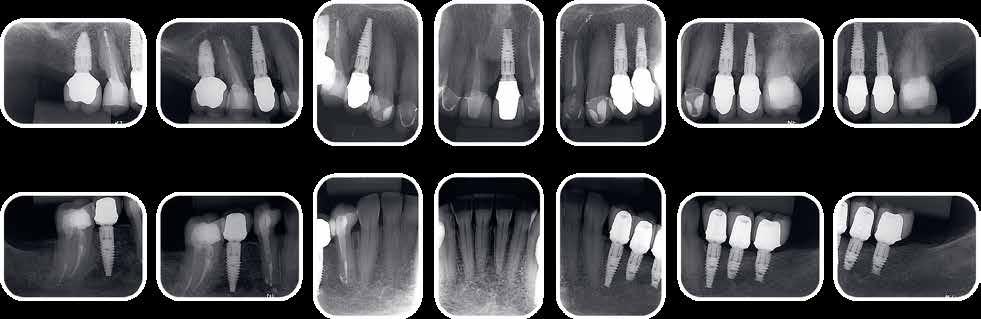

10. ábra. A négyéves kontroll alkalmával készült röntgenfelvételek. (A): A metszőfogakról készült koronafelvétel. (B): A jobb oldali szemfog és első kisőrlőfogról készült koronafelvétel. (C): A bal oldali szemfog és első kisőrlőfogról készült koronafelvétel.